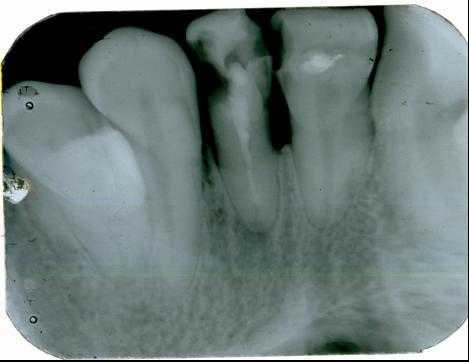

Рис. 1. Диагностический и измерительный снимки зуба 36, выполненные в прямой (а) и дистально-эксцентрической проекции (б). 36 — хронический апикальный периодонтит (К04.5) с характерными изменениями на мезиальном корне.

Рис. 3. Внутриротовой снимок зуба 24, хронический периапикальный абсцесс (К04.6), визуально определяется зона деструкции костной ткани с характерным перифокальным склерозом.

Рис. 4. Внутриротовой снимок зуба 44, радикулярная киста (К04.7), воспалительная ремоделяция перифокальной костной ткани отсутствует (пояснение в тексте).